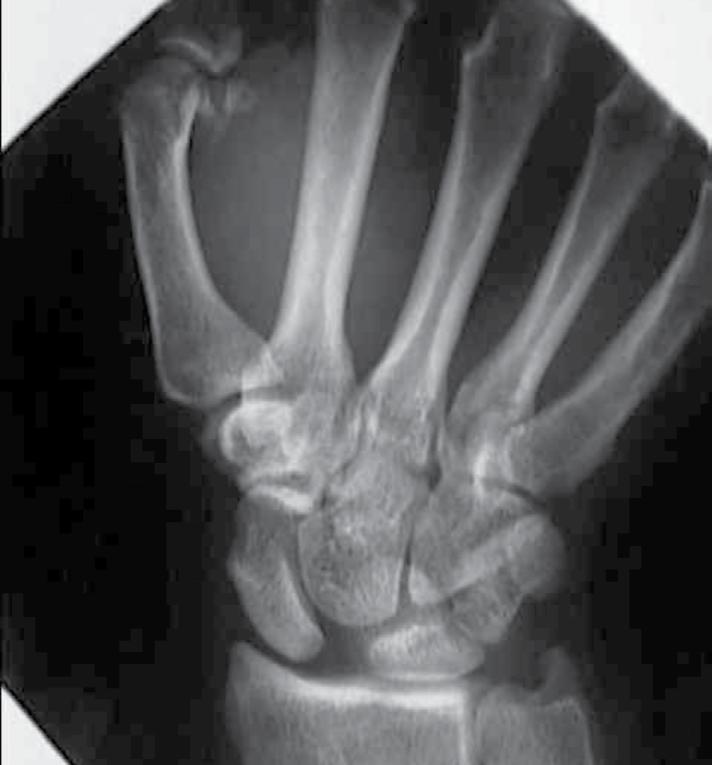

38-årig man som inkommer efter ett fall mot utsträckt arm, ömmar över distala radius och handroten. På misstanke radiusfraktur göres rtg som visar denna bild.

a. Diagnosmisstanke? (1p)

b. Vidare utredning? (1p)

c. Behandling? (1p)

a. Scapholunär dissociation.”Terry Thomas” sign; vidgning mer än 3 mm, ökad scapholunär vinkel

b. Ev provokationsröntgen.

c. Akut behandling med scaphoideumgips inkl tummens basfalang, inom 3 veckor kan öppen reposition och ligamentsustur göras, alt sluten reposition och stiftning.